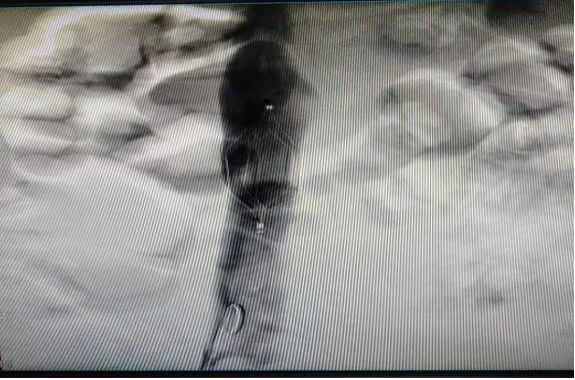

(7)2018年11月28日开展第一例下腔静脉滤器植入术。

患者:魏某  男性  52岁 平陌镇

图片

术前

术后